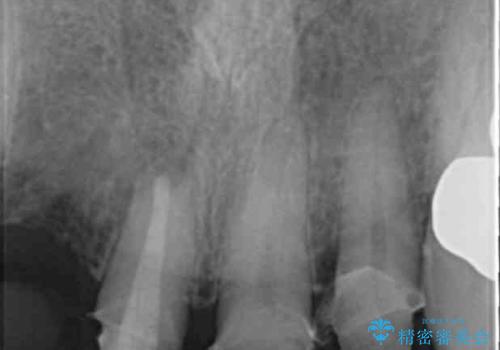

- 前歯の痛み・排膿・ぐらつきの改善を求めて来院されました。

視診・X線写真検査より根尖性歯周炎が認められ再治療が必要な状態です。

再根管治療を行うべくクラウン除去を行ったところ、右上側切歯に保存不可能な垂直性の破折が認められたため抜去が必要になりました。

即切歯の抜歯を行う場合犬歯を含めたブリッジによる補綴計画を立てることが多いですが、今回は犬歯から大臼歯にかかる大きなブリッジが既に装着されていたため予算とご希望を相談し前歯のみの延長ブリッジ補綴で治療を行っていくこととしました。